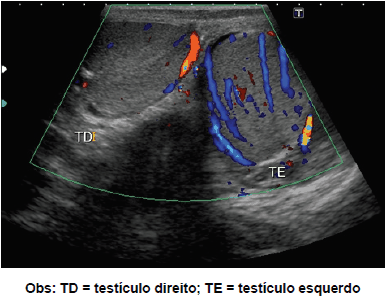

Sexo masculino, 18 anos, com dor escrotal há 18 horas. O testículo direito mediu 5,1 x 3,7 x 2,7 cm e o esquerdo 5,5 x 4,1 x 3,5 cm. Assinale a alternativa que apresenta a hipótese diagnóstica mais provável.